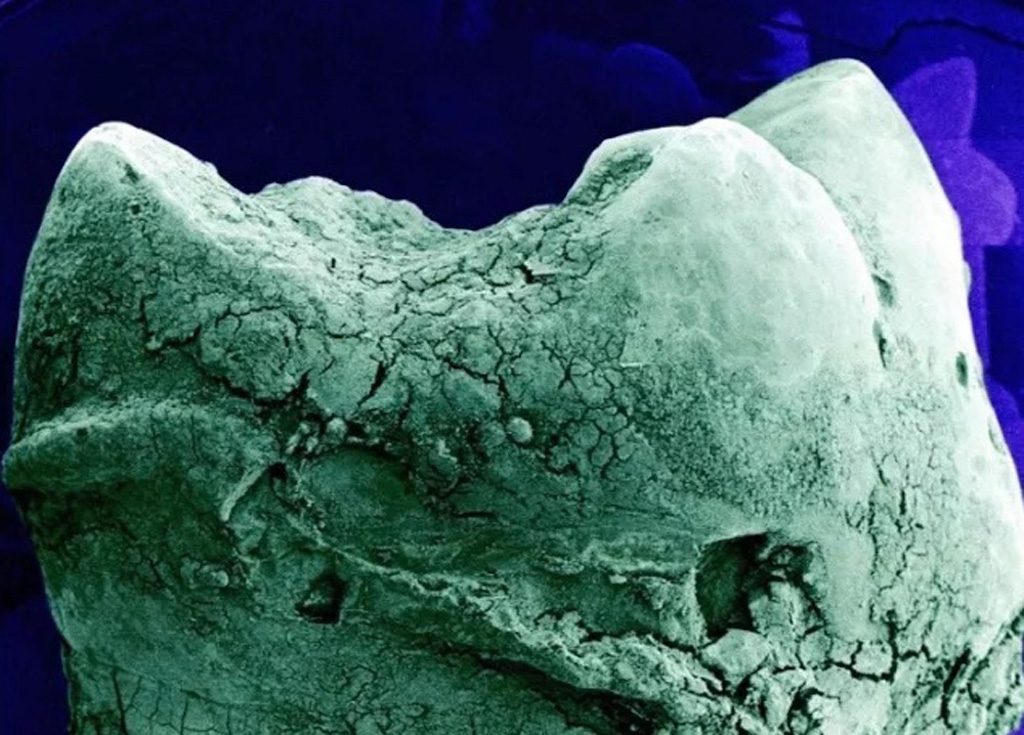

Primer punto, el alto grado de detalle que tienen las fotos. Se nos dificulta concebir un ojo, un óvulo, un pulmón, el iris del ojo, la célula capilar del oído, como unidades separadas y no como partes de un todo.

Ahora, comencemos el recorrido. Disfrutemos de estas imágenes, permitiéndonos experimentar la fascinación, la impresión o la repulsión, sabiendo que, mirado tan de cerca, nuestro cuerpo puede resultarnos más parecido a una obra de arte abstracto que a la experiencia de tener un cuerpo.